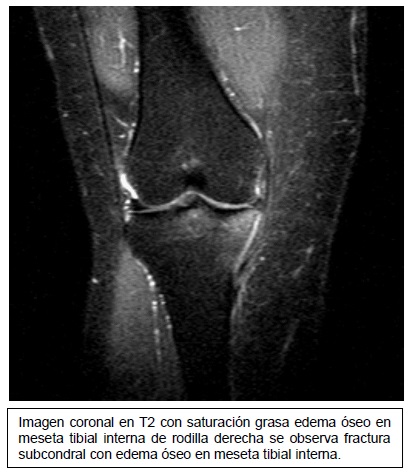

Imagen coronal de secuencia potenciada en T2 con saturación grasa de la rodilla derecha en paciente con lesión por traumatismo en valgo. Edema óseo en la

Fuente: https://epos.myesr.org/posterimage/esr/seram2014/124014/mediagallery/577012